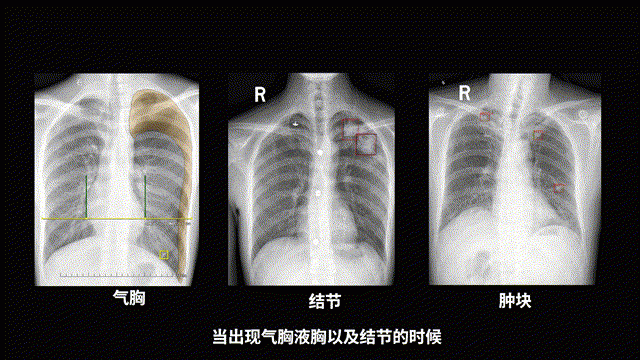

例如,在患者拍完 DR 胸片以后,联影智能的胸片预警系统能智能化识别异常影像征象,迅速提示危急值。这有助于医生及时采取措施,避免错过救治关键时刻,确保危急重症患者得到最佳的诊疗时机。